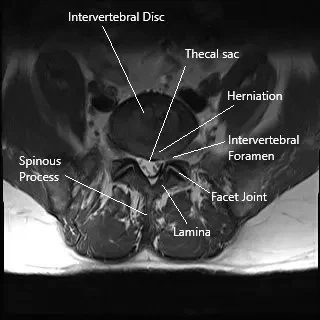

La columna lumbar consta de cinco vértebras (L1-L5) con discos intervertebrales entre ellas que actúan como amortiguadores. La médula espinal atraviesa el canal espinal, y los nervios se ramifican desde la médula a través de pequeñas aberturas llamadas forámenes. Estos nervios transmiten señales a varias partes del cuerpo, incluidas las piernas y los pies. Cuando un disco se hernia, puede comprimir estos nervios, provocando dolor y disfunción en las extremidades inferiores.

- MRI: La técnica de imagen estándar para visualizar hernias discales, compresión nerviosa y otros problemas de columna.